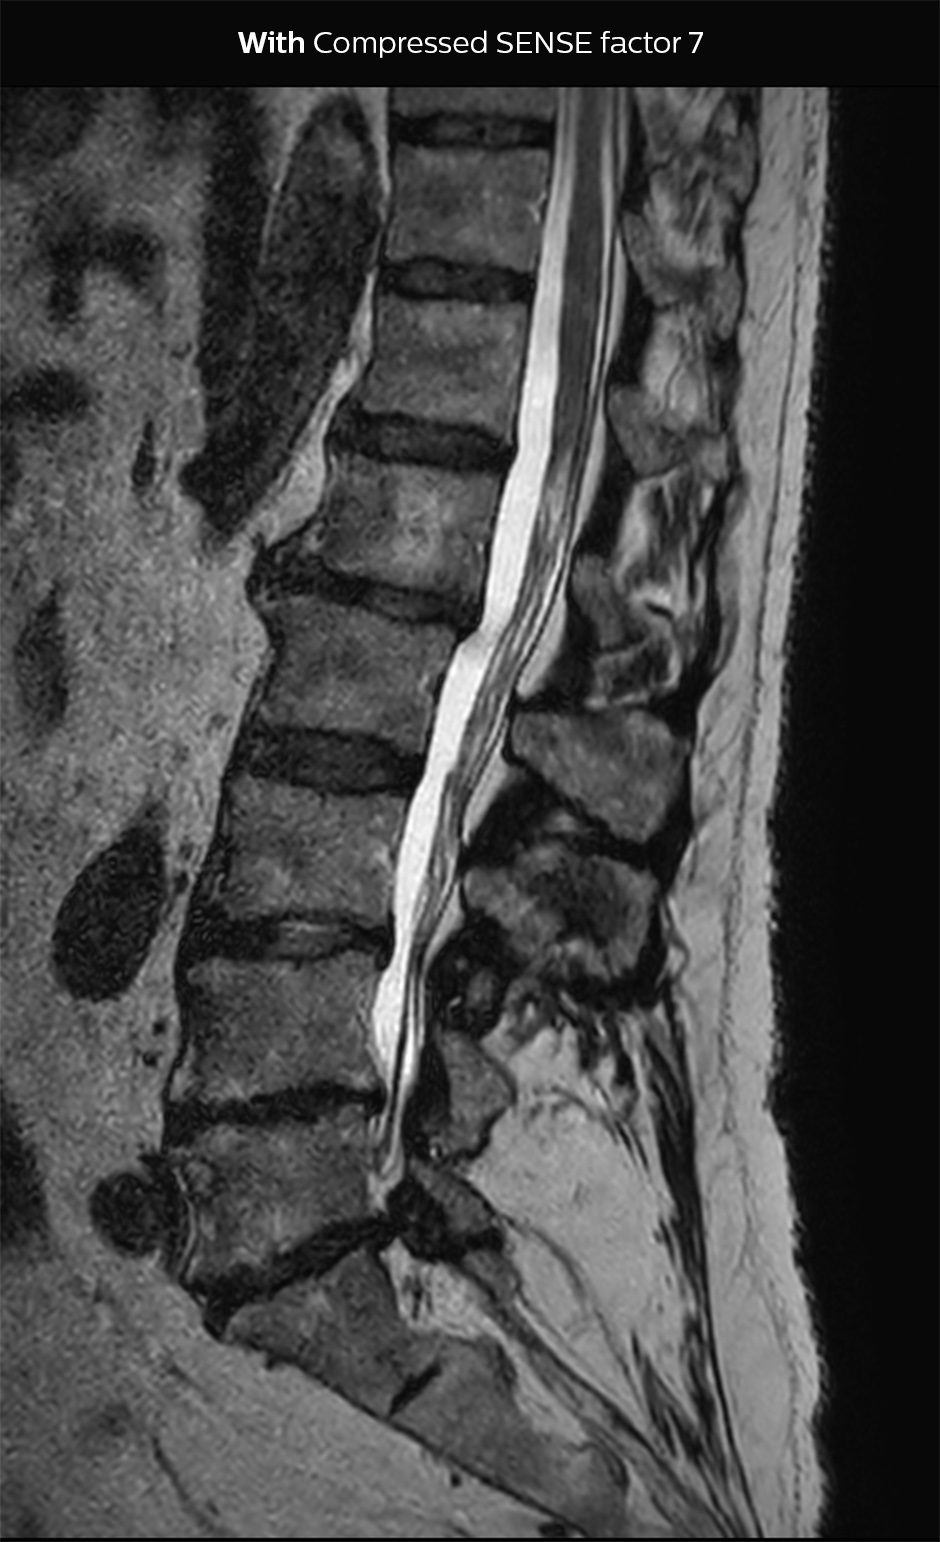

“Our aim for the spine is to use Compressed SENSE to help us make the switch to using 3D SpineVIEW. In lumbar spine, for example, we can reduce scan time for 3D T2W SpineVIEW by 27% to 4:46 minutes, voxel size 0.8 x 0.8 x 1 mm."

In this example Compressed SENSE has a 26% shorter scan time and improved spatial resolution simultaneously.

3D T2 SpineVIEW, scan time 6:29 min, voxel size 1 x 1 x 1.4 mm

3D T2 SpineVIEW, scan time: 4:46 min, voxel size 0.8 x 0.8 x 1 mm